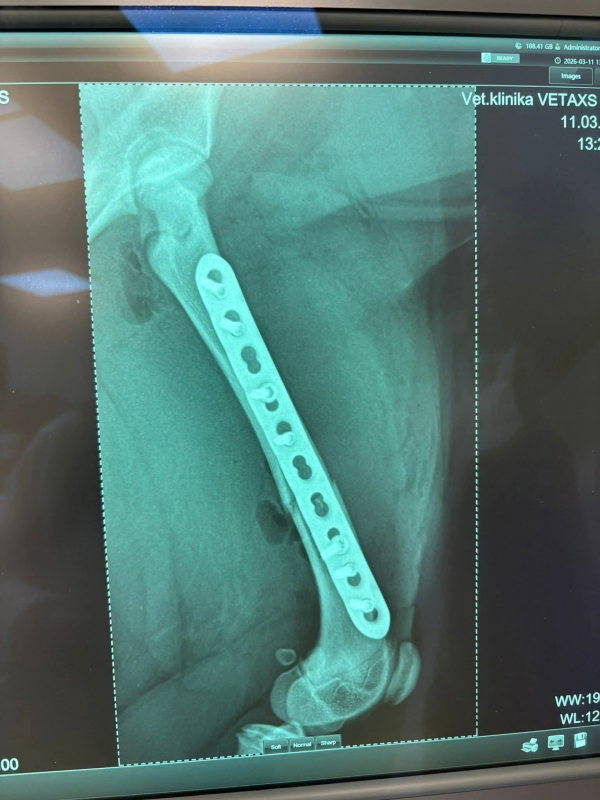

12.3.2026

DOLORES má po operácii ♥. Ďakujeme všetkým za pomoc ♥♥♥. Držte malej palce aby bola čoskoro fit :)

14.3.2026

Dolores po operácii pozdravuje. Zotavuje sa výborne a rýchlejšie ako sme mysleli ♥♥♥